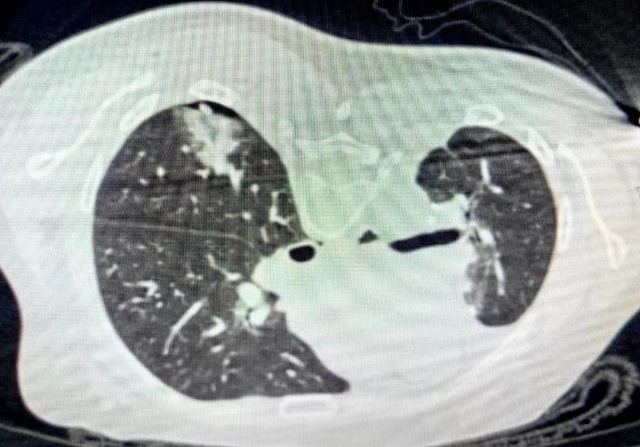

不幸的是,今年2月底右下肺又新长出6mm的肺癌。因为朱阿姨已经历过两次外科手术,切除了三“块”肺组织,如果再次外科手术治疗,显然不是最好的选择,这个时候到底改怎么治疗成为摆在医生面前的难题。

右下肺6mm肺癌,如箭头所示,不易发现

“近年来,肿瘤消融治疗发展迅速,已成为继手术、放疗、化疗、靶向治疗和免疫治疗之后又一重要的肺癌治疗手段。”西南医科大学附属医院呼吸与危重症医学科黄成亮副教授介绍,肺癌微波消融治疗通俗来讲,也可以叫一针“烧死”肺癌,就是把微波消融针,在CT引导局部麻醉下,穿刺到肺癌病变区域,通过微波产生的高温,在几分钟内使肺癌细胞发生凝固性坏死,类似于微波炉加热饭菜一样。微波消融后,在病灶周围形成1cm以上的毛玻璃影,往往表明这个肿瘤被完全杀灭。

由于肺时时刻刻在呼吸,而下肺的呼吸运动比较大,且病灶只有6mm,挑战性极大,黄成亮副教授在CT引导下,精准的把一根直径约2mm的消融针插入肿瘤病灶,很快消灭掉了右下肺的肿瘤。手术助手张明博士配合完美,消融结束后再次进行CT检查,确保病灶已经被灭活杀死,最终手术圆满成功。